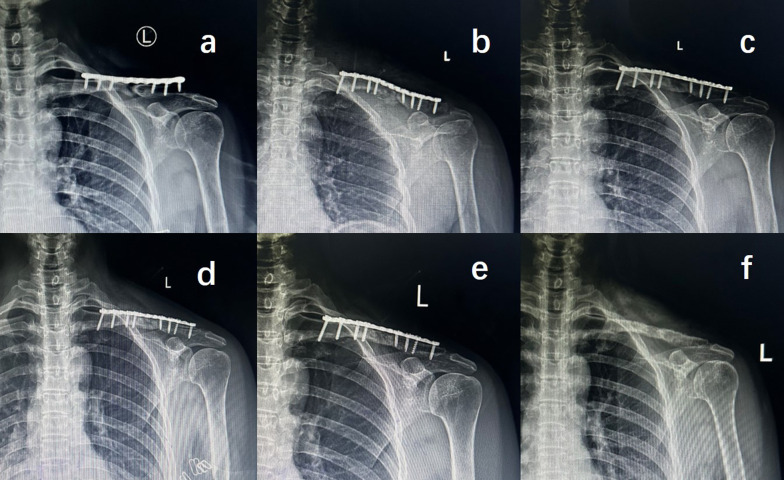

Background: Open reduction, superior plate (SP) fixation, and autologous cancellous granular bone grafting (ACGBG) are common strategies for treating clavicular midshaft atrophic nonunion (CMAN). We aimed to compare the radiological findings and clinical effects of two autologous cancellous bone grafts (ACBGs) and those of single SP fixation, to treat CMAN.

Methods: This retrospective study comprised 62 patients admitted to our hospital with CMAN (ACGBG with single SP fixation between March 2012 and October 2017, 32 patients; autologous cancellous structured bone grafting [ACSBG] with single SP fixation between November 2017 and May 2021, 30 patients). Patient visual analog scale (VAS) scores for pain and disability of the arm, shoulder, and hand (DASH) scores, obtained preoperatively and at final follow-up, were recorded and analyzed. Statistical differences between the ACGBG and ACSBG groups were assessed using Fisher's exact and two-sample independent t tests.

Results: No statistically significant differences were observed between the two groups in terms of patient demographics or the incidence of complications. VAS and DASH scores decreased significantly from the preoperative day to 9 months postoperatively in both groups, but this difference was not statistically significant at final follow-up. However, at 3 and 6 months postoperatively, compared with mean VAS and DASH scores in the ACGBG group, the ACSBG group showed lower pain and dysfunction scores (p < 0.05). The mean fracture healing times were 15.2 (range, 12-20) and 18.6 (range, 12-32) weeks in the ACSBG and ACGBG groups, respectively (p = 0.01). One case of plate breakage occurred in the ACGBG group at 5 months postoperatively, with recovery following ACSBG revision with single SP fixation.

Conclusions: ACSBG combined with single SP fixation is a promising and effective alternative technique for promoting bone union and postoperative early functional rehabilitation in treating CMAN.